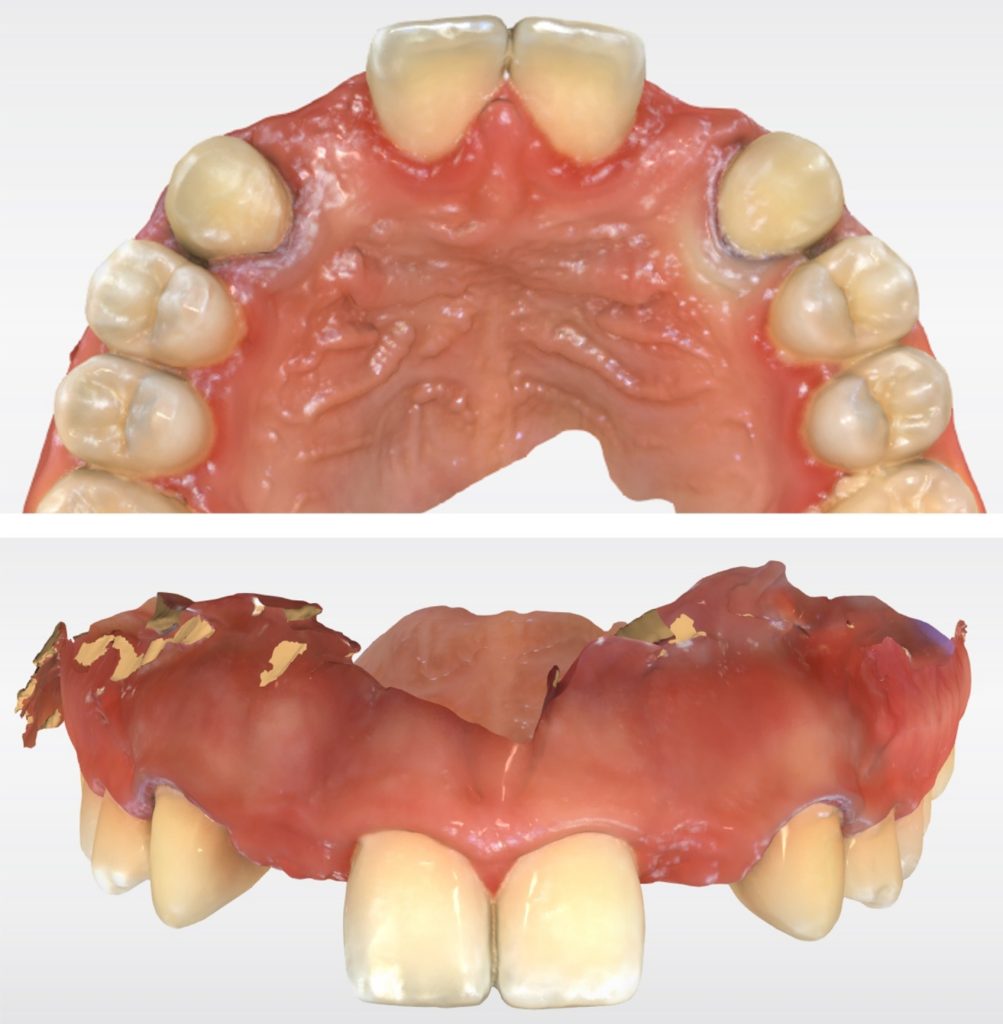

Solution #1: Canine Substitution for Missing Lateral Incisors

Canine substitution is the least invasive option and a popular alternative, but it often poses esthetic and functional challenges that need to be considered and cleared (Fig. 1). From an esthetic standpoint, the canine’s shape and shade must be considered. From a contour standpoint, the width of the canine should be evaluated because they are generally larger than lateral incisors.

However, the most critical aspect to manage is the CEJ width because it cannot be narrowed. The wider the tooth at the CEJ, the more difficult it is to make a canine look like a lateral incisor. Moreover, canines typically present with a very distinctive root eminence, and if it is particularly accentuated, it could become yet another esthetic challenge — one commensurate with the patient’s lip mobility.

There is no major esthetic concern for patients where a low lip line conceals the gingival outline. Still, if there is high lip mobility and the gingival outline is not concealed, such an eminence could represent an unacceptable esthetic problem.

From a shade standpoint, canines usually are the teeth with the most saturated chroma in the maxillary arch, which often creates an esthetic challenge where this oversaturation is evident.

Consequently, considering these aspects, the ideal clinical scenario for canine substitution would be in patients with smaller shaped canines that are not oversaturated with chroma and in patients who display low lip mobility.